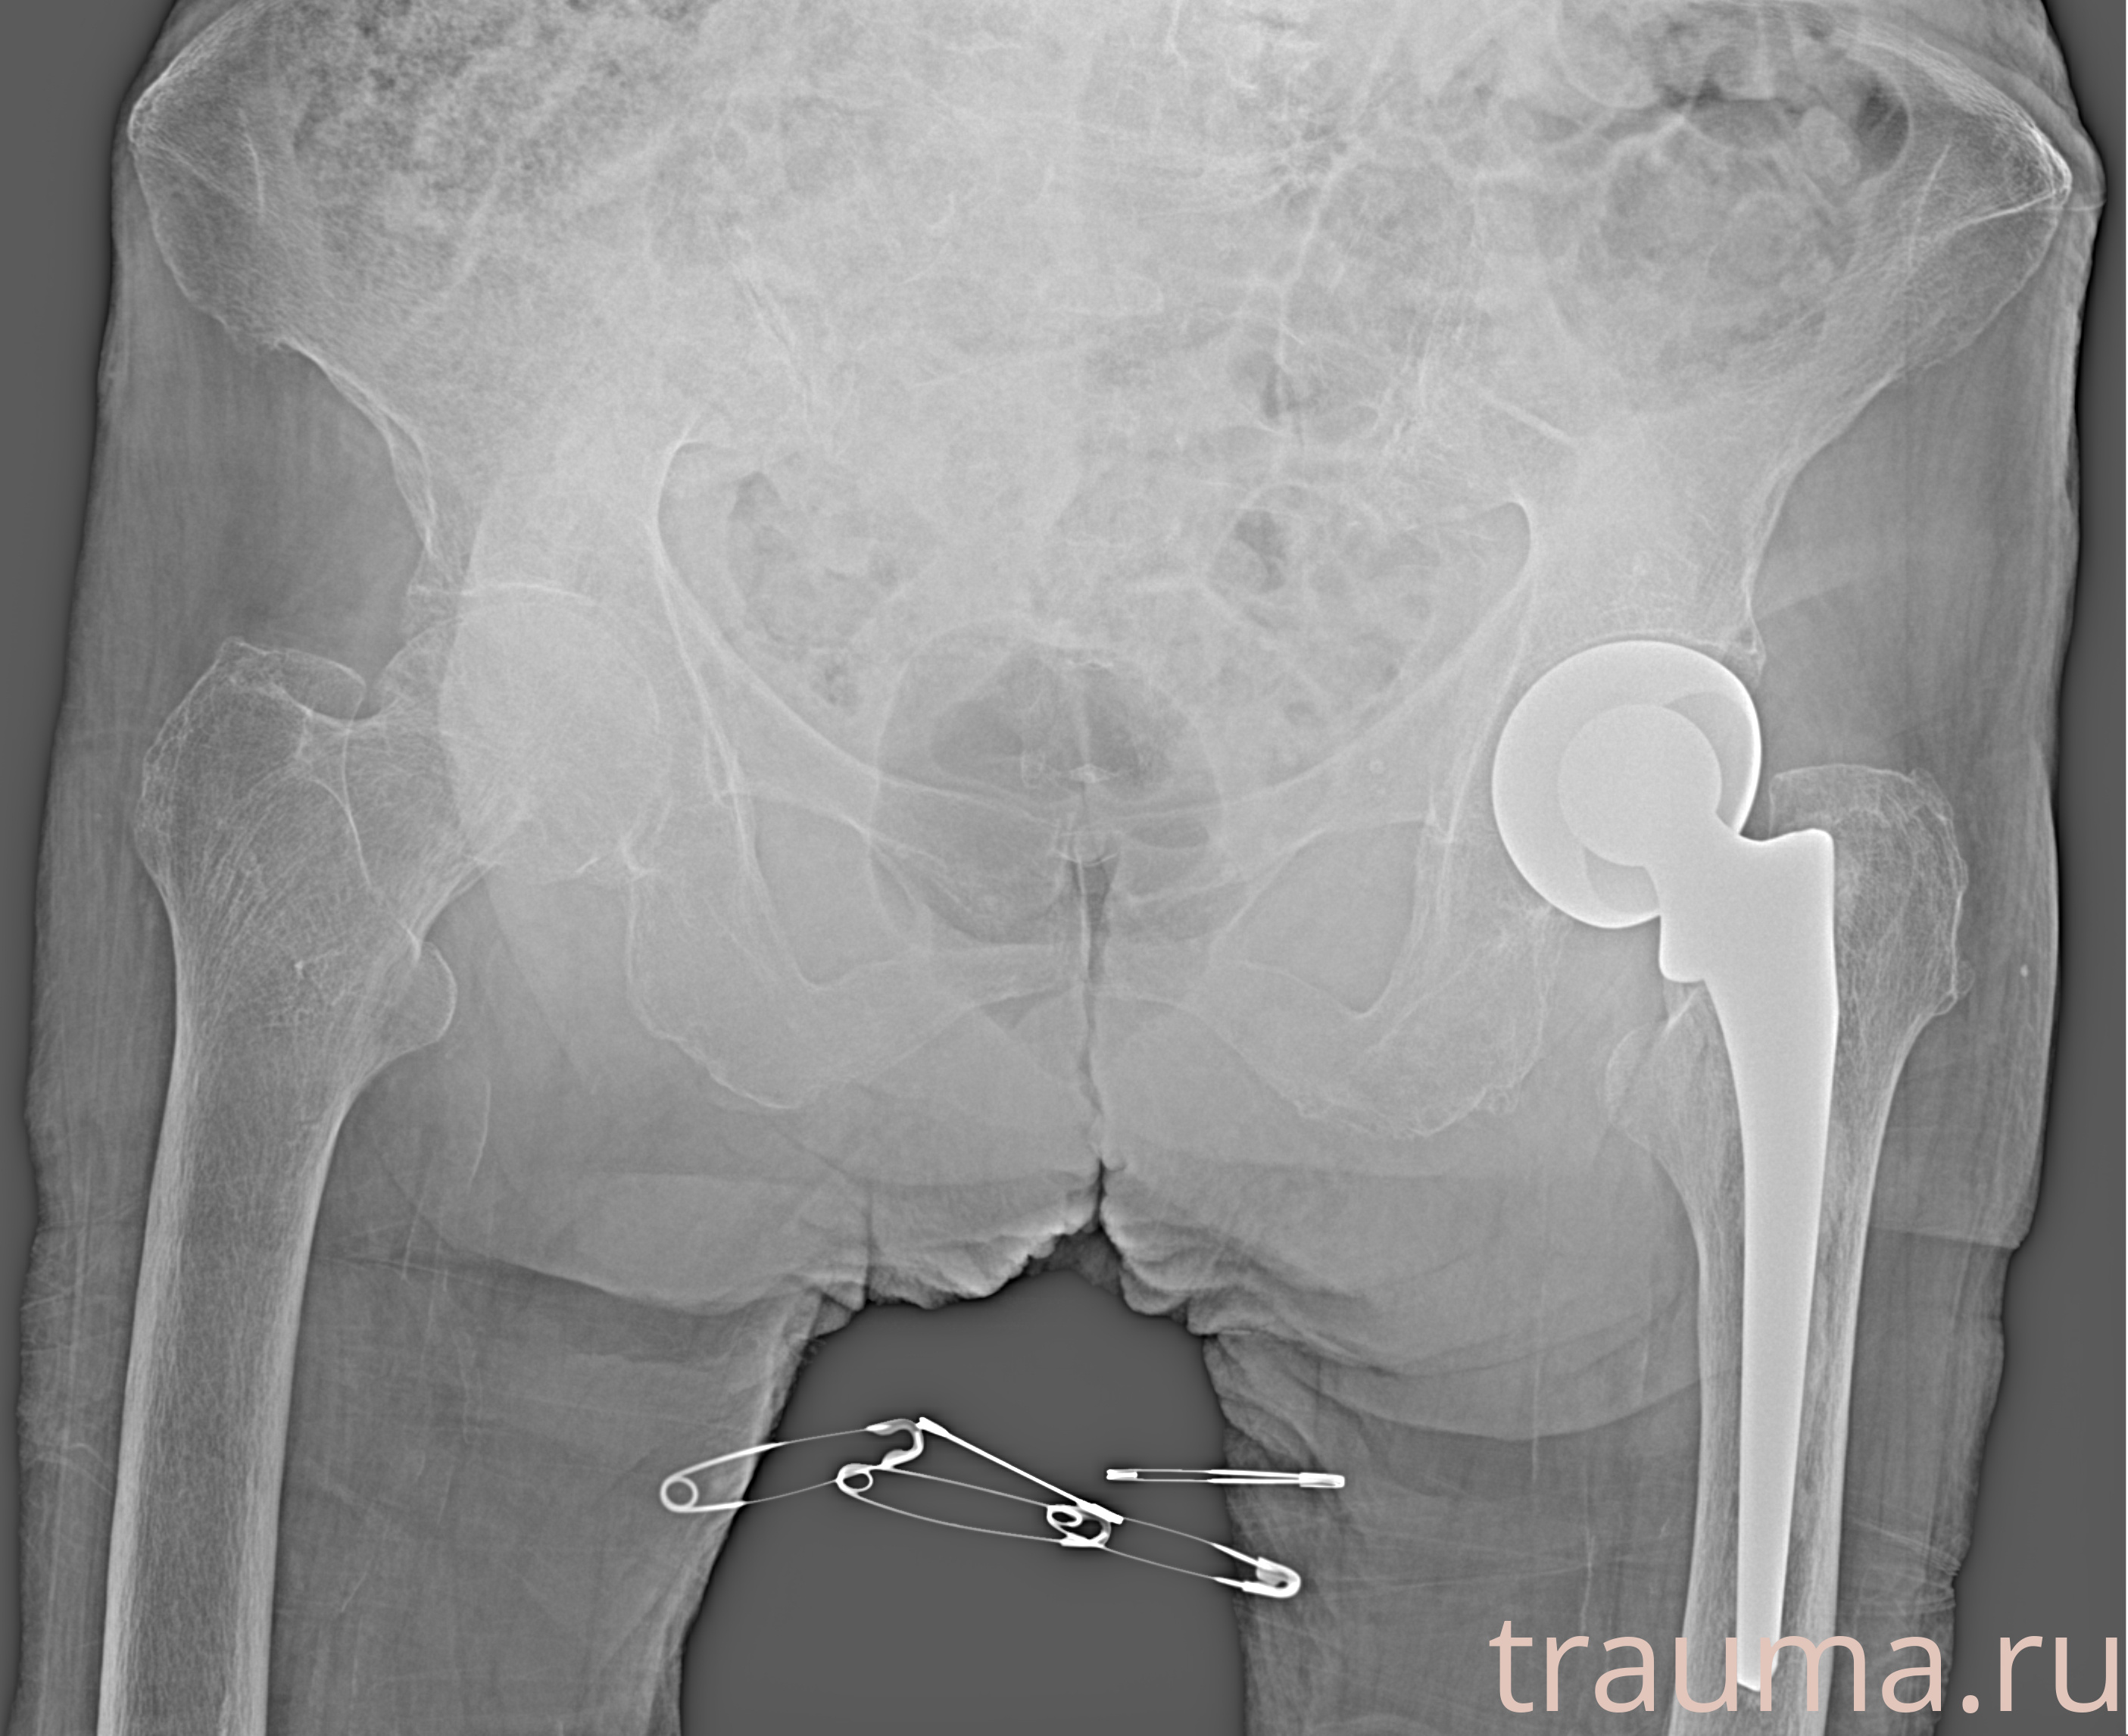

Рентген на дому: по вашему адресу приезжает врач-рентгенолог, травматолог-ортопед с мобильным рентгеновским аппаратом, проводит диагностику травмы или заболевания, делает необходимые рентгенограммы, дает рекомендации по дальнейшему лечению. Получить качественные снимки в домашних условиях возможно благодаря уникальной методике, разработанной МосРентген Центром для института  Склифосовского